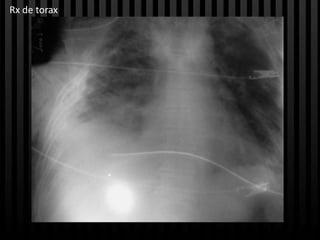

Rx de torax

Caso clínico • 57 años • Cuadro clínico de 45 días • Fiebre intermitente, disnea de pequeños esfuerzos, dolor torácico, astenia, adinamia, tos con expectoración purulenta, dificultad respiratoria. • Falla ventilatoria = ventilación mecánica = entubación prolongada = traqueostomia • Rx derrame pleural bilateral = toracostomia bilateral = remisión a 3 nivel. Antecedentes: Patológicos: neumonía hace 2 años Farmacológicos: - Toxicos: -

Caso clínico Examen físico: • Regular estado general • SV: Ta: 149/74 fc: 135 fr: 19 Spo2 99% Peso: 60 kg • mucosa palpebral pálidas • Traqueostomia funcional • RsCsRs, pulmones con disminución de murmullo vesicular bibasal, toracostomia bilateral • abdomen normal, extremidades eutróficas, neurológico sin déficit • Glasgow 14/15, llenado capilar <2 segundos